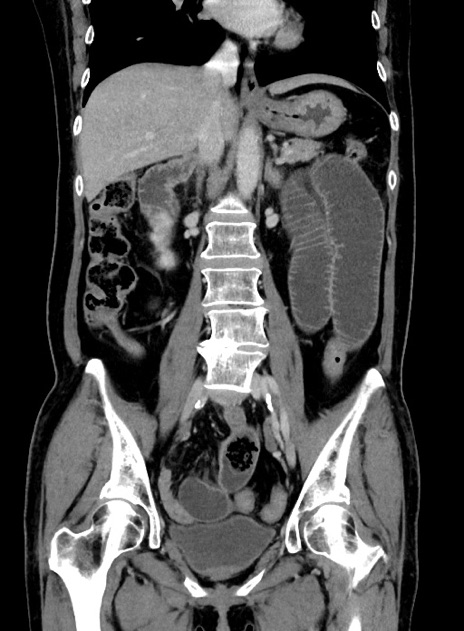

症例9(冠状断像)

【症例】 60歳代女性

【主訴】むかつき、みぞおちの痛み

【現病歴】3日前よりむかつきがあり、食事がとれない。

【既往歴】糖尿病

【身体所見】発熱なし、心窩部圧痛軽度あるも、腹膜刺激症状なし。

【データ】WBC 7400、CRP 1.92